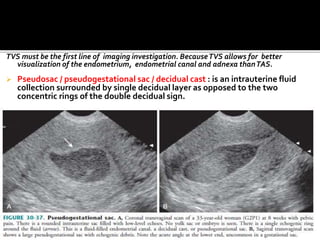

TVS must be the first line of imaging investigation. BecauseTVS allows for better

visualization of the endometrium, endometrial canal and adnexa thanTAS.

 Pseudosac / pseudogestational sac / decidual cast : is an intrauterine fluid

collection surrounded by single decidual layer as opposed to the two

concentric rings of the double decidual sign.